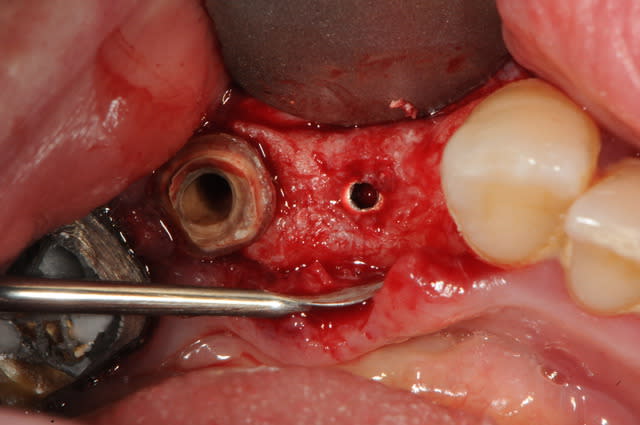

la preuve par 9...

si ça te convient pas... je vois pas ce qui marcherait mieux..

3ième photo , c'est j+3 mois.

D57, t'avais mis un biomat? ou juste la membrane?

j'étais pas sur , mais oui, il y en a eu un.

pas de coté pour placer la membrane.

D57 dans un défaut à 1 mur tout marche ou presque , non ?